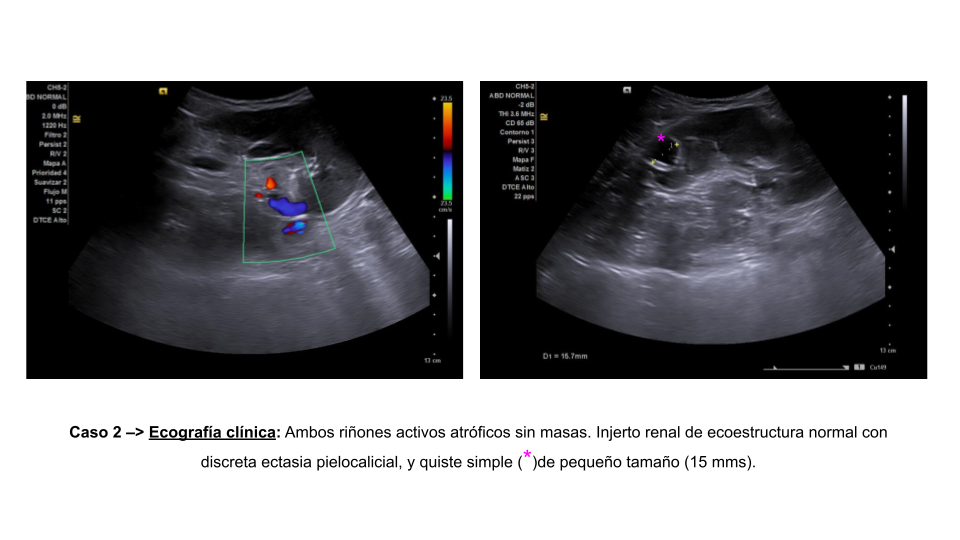

• Caso 2: Ambos riñones activos atróficos sin masas. Injerto renal de ecoestructura normal con discreta ectasia pielocalicial.